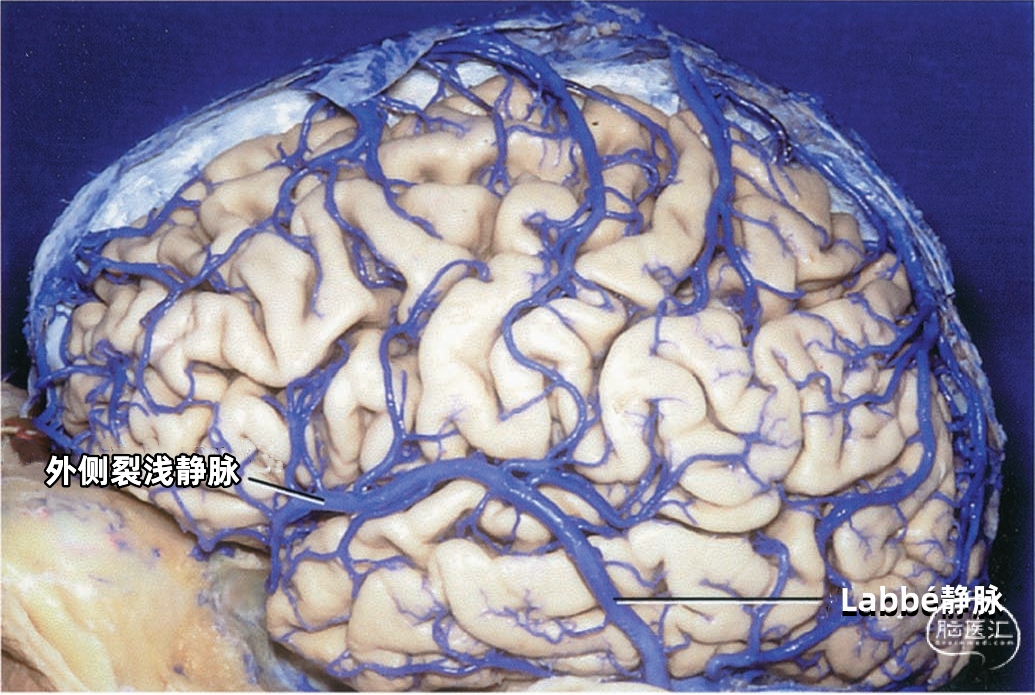

大脑外侧面最大的静脉是Trolard、Labbé、外侧裂浅静脉。 Trolard静脉是最粗大的吻合静脉,连接外侧裂静脉和上矢状窦。Labbé静脉则是连接外侧裂浅静脉和横窦的最粗大吻合静脉。外侧裂浅静脉沿外侧裂表面走行,而且主要沿蝶骨嵴汇入硬膜窦(蝶顶窦或海绵窦)。 虽然Trolard、Labbé静脉和外侧裂浅静脉大小可能相同,但更常见的是其中一支或两支血管比较粗大,而剩下的则细小甚至缺如。通常左右两侧血管的大小并不对称。

下图示外侧裂浅静脉是主要引流静脉。

下图示Labbé静脉为主要引流静脉

▼2.Labbé静脉

Labbé静脉也称下吻合静脉,是跨越颞叶外侧,连接外侧裂与横窦之间的最大吻合静脉。它通常起自外侧裂中部,行向后下,进入横窦前部。 Labbé静脉经过颞叶表面的位置有可能非常靠后甚至位于颞叶的最后界,或非常靠前达颞叶前1/3的外侧面。在此研究的20例半球中,12例Labbé静脉位于颞中静脉水平,6例位于颞后静脉水平,2例位于颞前静脉水平。有时会有两条Labbé静脉,其中后支通常会粗大一些。

▼3.外侧裂浅静脉

外侧裂浅静脉通常起自外侧裂后端,沿外侧裂唇行向前下。它可能以两支起始,但通常在沿蝶骨嵴进入静脉窦之前融合为一支。 外侧裂浅静脉接受额外侧裂静脉、顶外侧裂静脉和颞外侧裂静脉的回流,并经常与Trolard静脉和Labbé静脉相吻合。它穿经覆盖外侧裂前端的蛛网膜,在蝶骨嵴内侧部下方加入蝶顶窦,或直接进入海绵窦。它也有可能离开外侧裂,围绕颞极,进入中颅窝底的硬膜窦,引流入岩上窦,或通过蝶骨的小孔出颅与翼静脉丛相交通。 如果外侧裂浅静脉细小或缺如,则相邻的静脉将代替引流其区域。起自外侧裂上唇的静脉,向上引流加入进入上矢状窦的静脉;起自外侧裂下唇的静脉,直接向后下,汇入颞叶下方的硬膜窦。如果外侧裂浅静脉的中部缺如,则静脉前部加入蝶骨嵴的硬膜窦,而后部则加入Trolard和Labbé吻合静脉。

下图示(左侧)粗大的外侧裂浅静脉,只与上矢状窦有较小的沟通支。但此区域的主要静脉引流通过颞叶中部的Labbé静脉